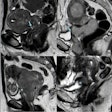

Sequences included in the study MRI protocol: (a) coronal TIRM (turbo inversion recovery magnitude) sequence, (b) coronal T1-weighted sequence, (c) axial FLAIR (fluid-attenuated inversion recovery) sequence (head only), (d) axial T2-weighted fast spin-echo sequence (HASTE), (e) axial diffusion-weighted imaging (b-value 900), (f) an axial ADC map, (g) axial T1-Dixon water-only images before contrast agent, and (h) after administration of contrast agent.All figures courtesy of Dr. Myriam Keymling et al and European Radiology

Sequences included in the study MRI protocol: (a) coronal TIRM (turbo inversion recovery magnitude) sequence, (b) coronal T1-weighted sequence, (c) axial FLAIR (fluid-attenuated inversion recovery) sequence (head only), (d) axial T2-weighted fast spin-echo sequence (HASTE), (e) axial diffusion-weighted imaging (b-value 900), (f) an axial ADC map, (g) axial T1-Dixon water-only images before contrast agent, and (h) after administration of contrast agent.All figures courtesy of Dr. Myriam Keymling et al and European Radiology

Combinations of sequences were assessed in order to determine the optimal protocols. The analysis included turbo-spin echo (TSE) T1-weighted and inversion-recovery T2-weighted (TIRM) images of the whole body in coronal orientation, and T2-weighted (HASTE), diffusion-weighted (DWI), and T1-weighted DIXON images (pre- and postcontrast agent administration) from head to thighs in axial orientation. An additional fluid-attenuated inversion recovery (FLAIR) sequence was used for the skull only.